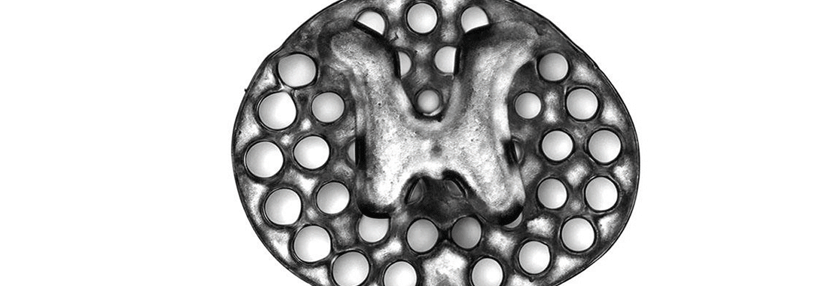

An den Querfortsätzen der LWS fixiert, stimulieren die Elektroden den Ramus dorsalis der Spinalnerven.

© Mainstay Medical

Einer der ersten Orthopäden, die das System hierzulande verwenden, ist Dr. Jan Schilling von der Abteilung für Wirbelsäulen- und Neurochirurgie am Krankenhaus Tabea in Hamburg. Infrage kommen Patienten mit chronischen unspezifischen Rückenschmerzen ohne Indikation zu OP oder spinal cord stimulation nach erfolgloser konservativer Therapie. Bei dem minimalinvasiven Eingriff platziert Dr. Schilling zwei Elektroden an den Querfortsätzen der LWS, die den Ramus dorsalis der Spinalnerven stimulieren. Über Koinnervation erreichen die Impulse die Tiefenmuskulatur der angrenzenden Wirbel. Die zugehörige Batterie mit Impulsgeber findet s.c. im Gesäß ihren Platz.